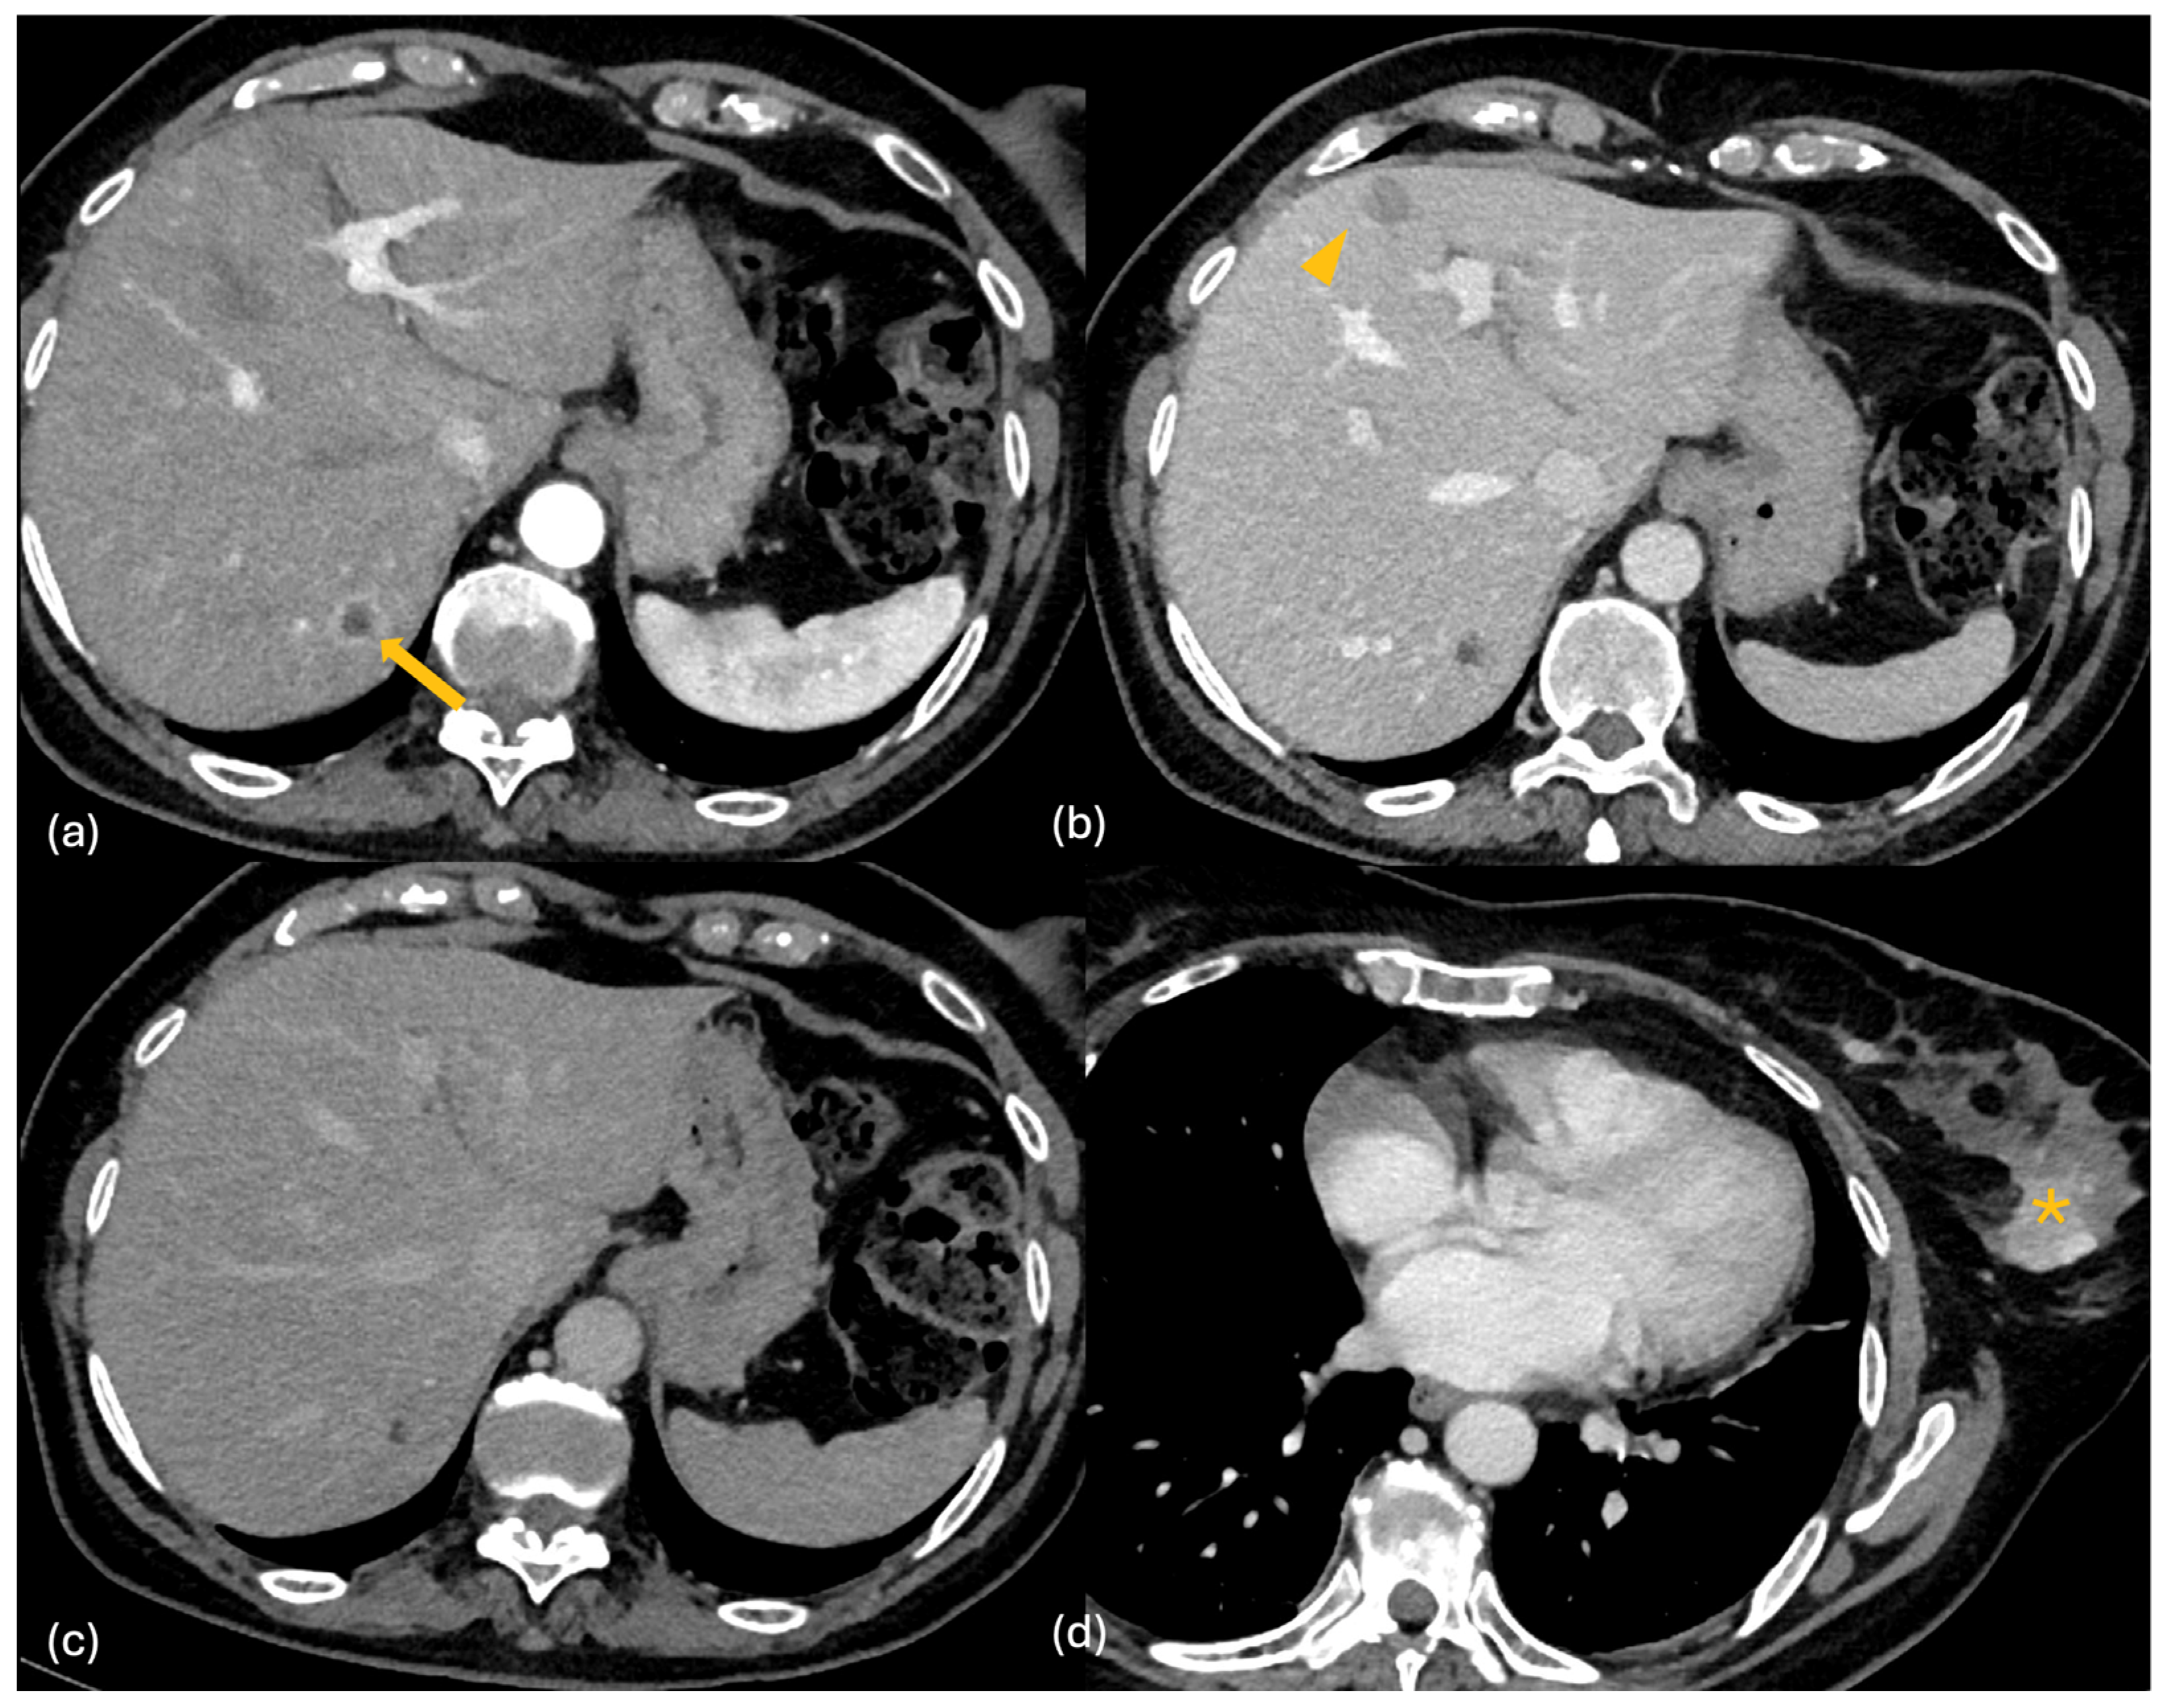

2.2. CT

2.3. MRI